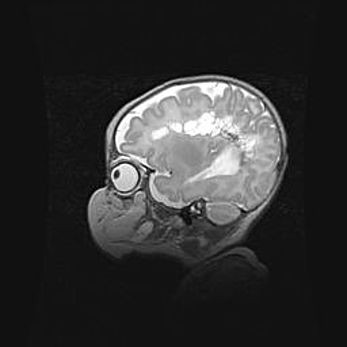

Мальформация Денди-Уокера. Киста задней черепной ямки.

Агенезия мозолистого тела.

Возраст: 2,5 месяца

Вес: 2420 г

Пол: женский

Окружность головы: 37 см

Срок гестации: 32 недели

Мальформация Денди—Уокера — редкий вид патологии ЦНС, представляющий собой врожденный порок развития каудального отдела ствола и червя мозжечка, ведущий к неполному раскрытию срединной (Мажанди) и латеральных (Лушка) апертур IV желудочка мозга. Для этогно синдрома характерна триада симптомов: гипотрофия червя мозжечка и/или полушарий мозжечка, кисты задней черепной ямки, гидроцефалия различной степени. В 70% случаев порок сочетается и с другими аномалиями головного мозга, в частности с агенезией мозолистого тела.